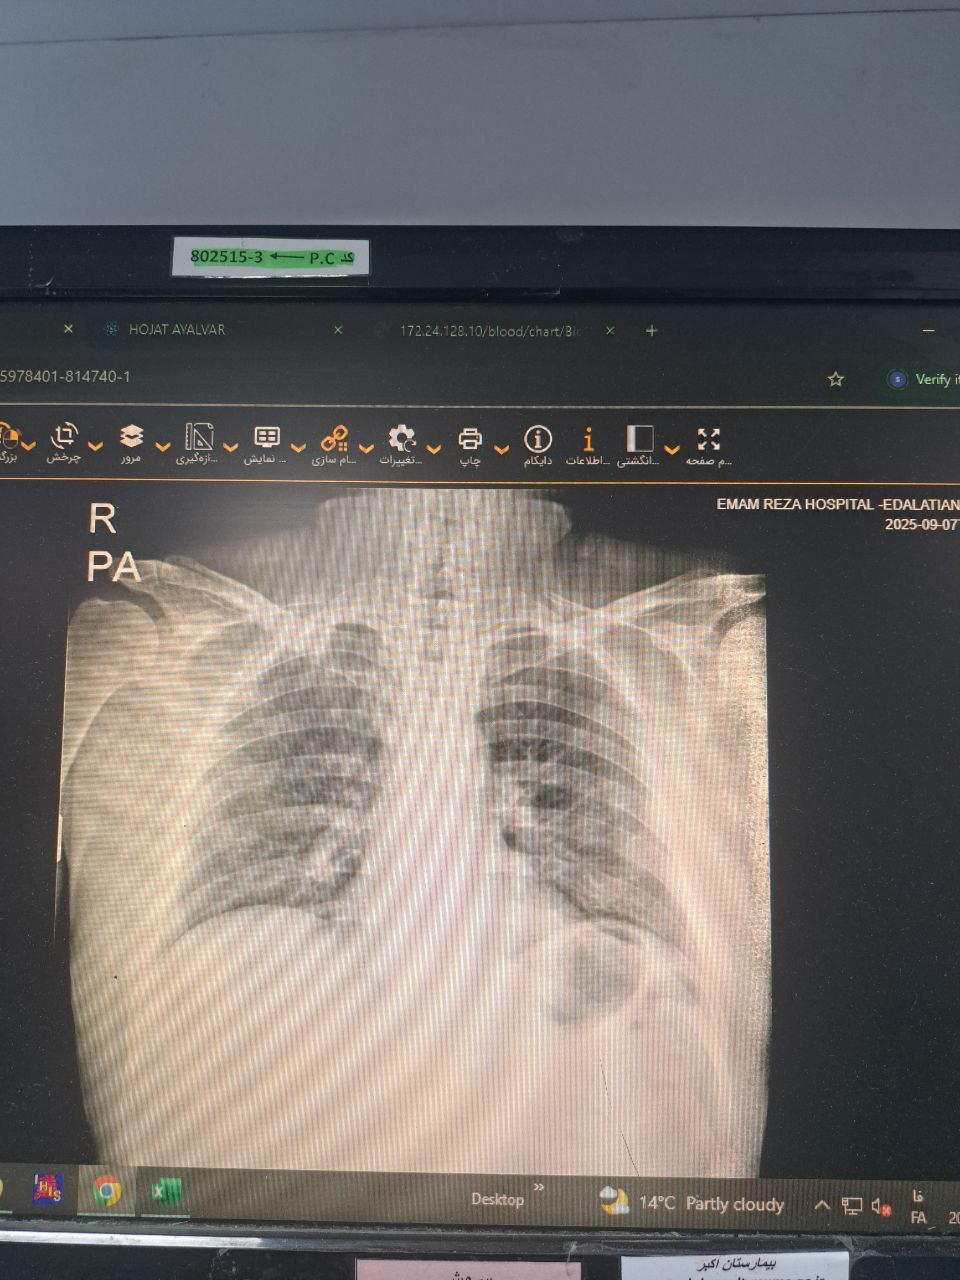

سمع ریه نرمال و فاقد ویز ورال

موکور مایکوزیس, X-Ray

X-Ray: